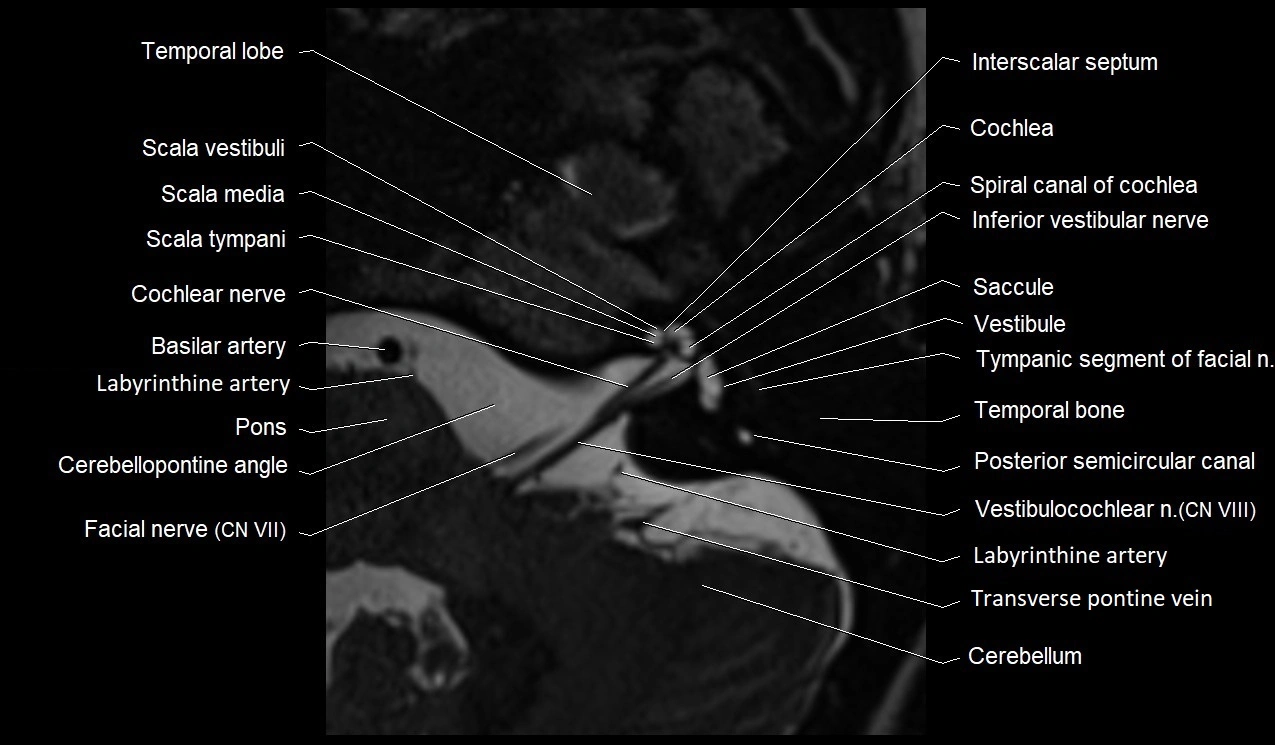

MRI images

image